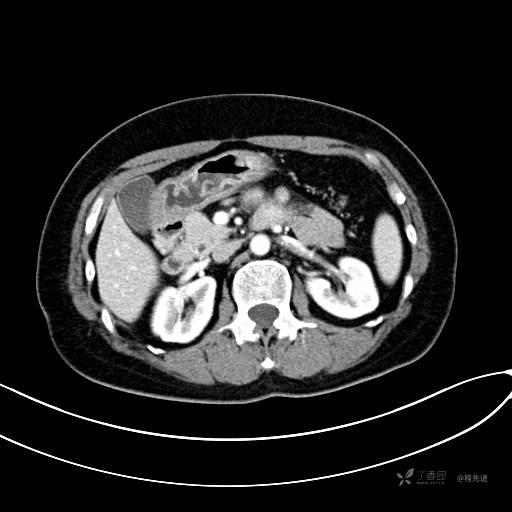

CT平扫